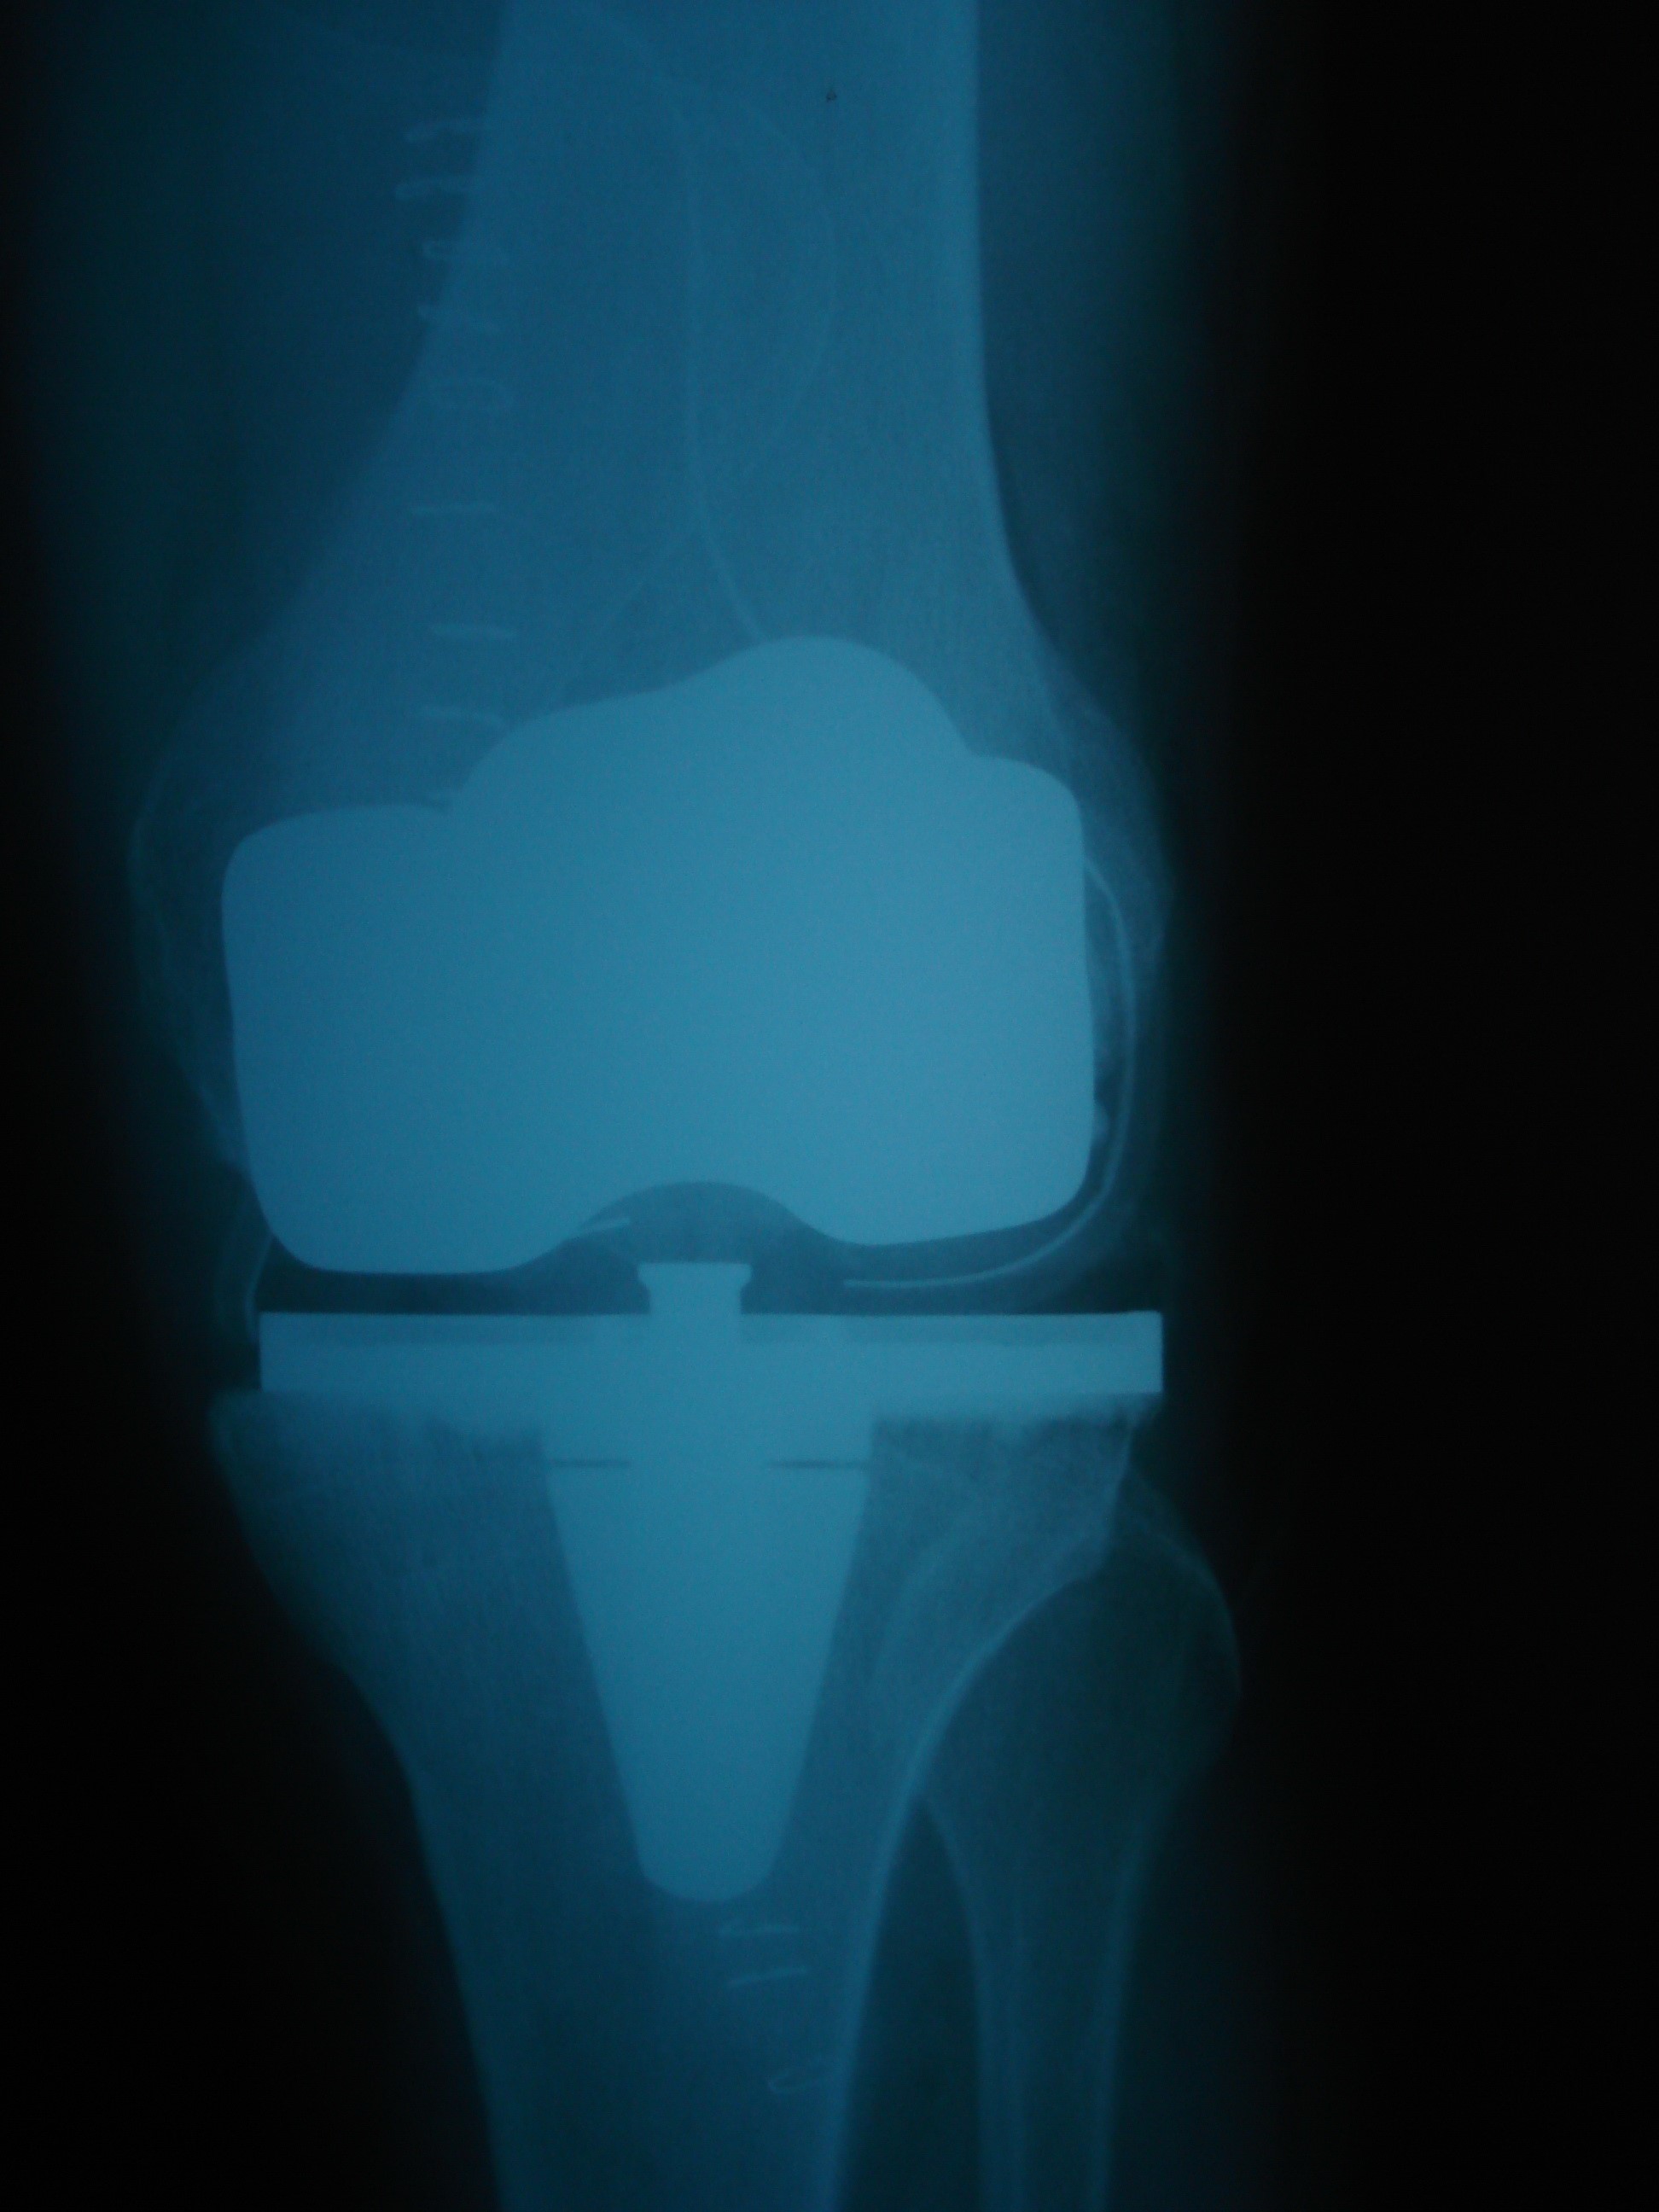

Eklem Protezleri

Total Diz Protezi

Aşınmış olan eklem yüzlerinin, suni eklemlerle değiştirilmesi durumudur. Günümüzde diz dışında pek çok eklemde başarı ile uygulanmaktadır.